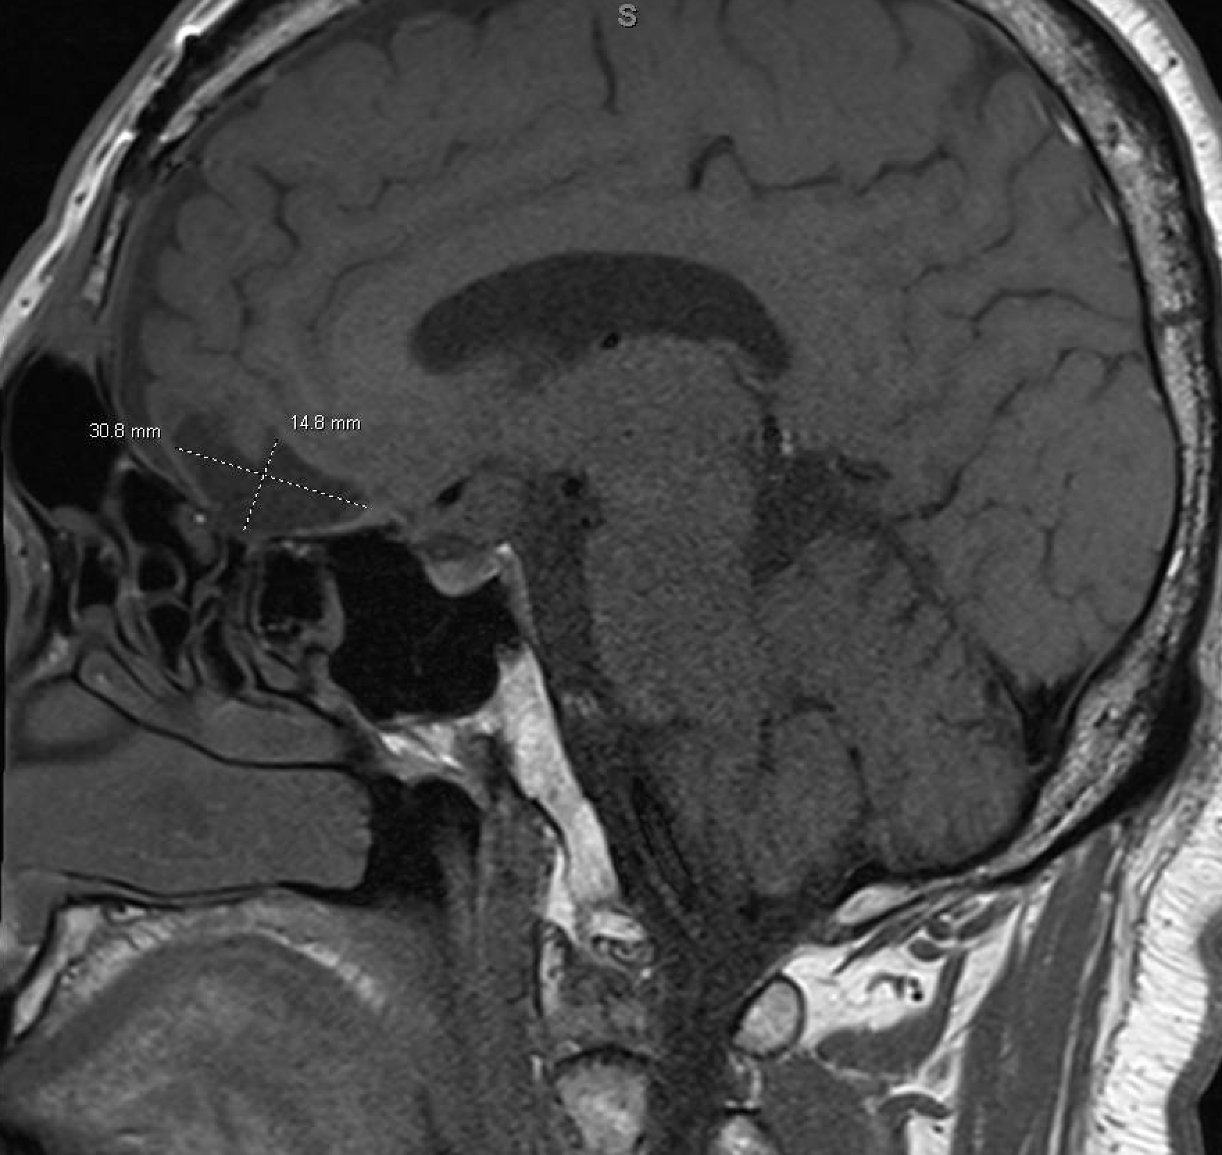

In August 2022, the patient presented again with visual deficits. Repeat MRI showed a 10.3 mm × 14.6 mm × 17 mm cystic mass in the suprasellar area with enhancing mural nodules, most likely related to craniopharyngioma that is causing mass effect on the optic chiasma (Figures 1, 2). He underwent an endoscopic endonasal transplanum transtuberculum approach to the middle fossa skull base with a resection of the middle cranial fossa skull base tumor. Pathology revealed papillary craniopharyngioma, CNS WHO grade 1. BRAF V600E mutation was identified. Subsequently, a CSF leak was present, and he underwent a CSF leak repair. He followed up with the surgical team who monitored for symptoms of clinical relapse. Importantly, the patient never went for radiation.

Figure 1

Sagittal brain MRI showing a 10.3 mm × 14.6 mm × 17 mm cystic mass in the suprasellar area with enhancing mural nodules, most likely related to craniopharyngioma, causing mass effect on the optic chiasma.